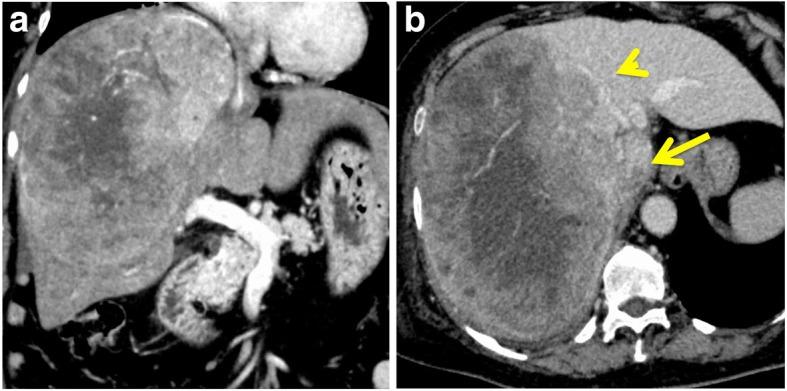

Tumor thrombectomy under cardiopulmonary bypass with heparin and electrical ventricular fibrillation prior to hepatectomy was successfully performed to prevent sudden cardiac arrest or pulmonary embolism in a 75-year-old woman with a huge HCC and TT in the right atrium. After the neutralization of heparin, right hepatectomy with tumor thrombectomy in the inferior vena cava was performed. The total operation time was 9 h, and the total blood loss was 8200 mL. The patient's postoperative course was uneventful, and she was discharged 14 days after surgery. One year after surgery, she is alive with HCC recurrence in the lung.